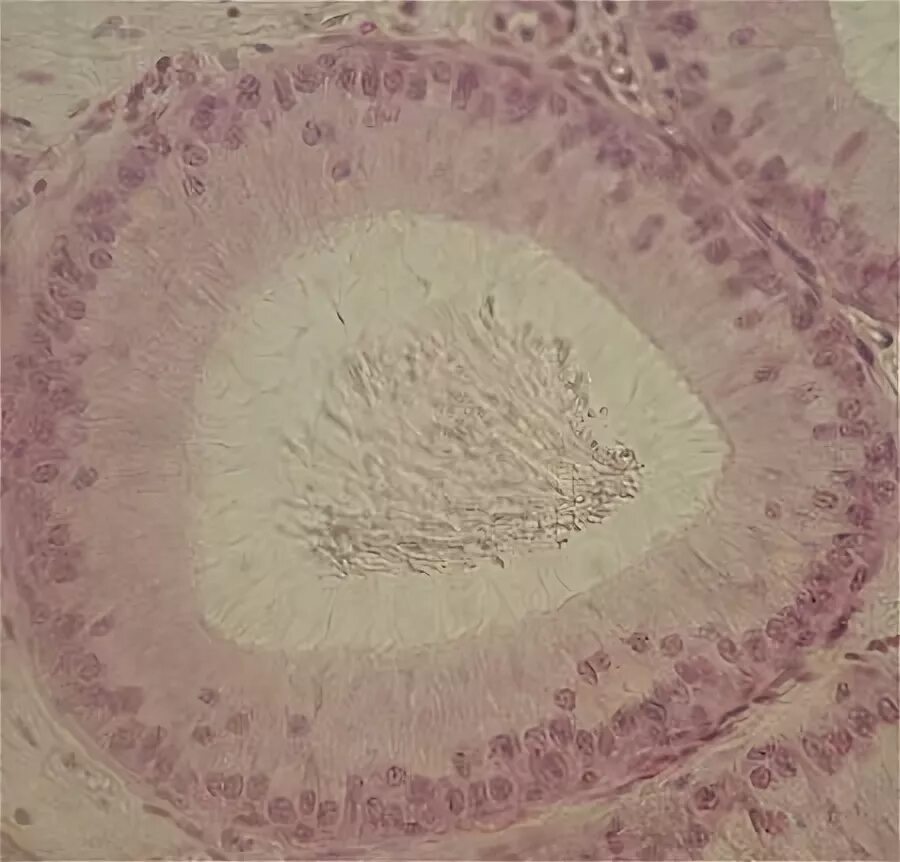

Придаток яичка гистология препарат